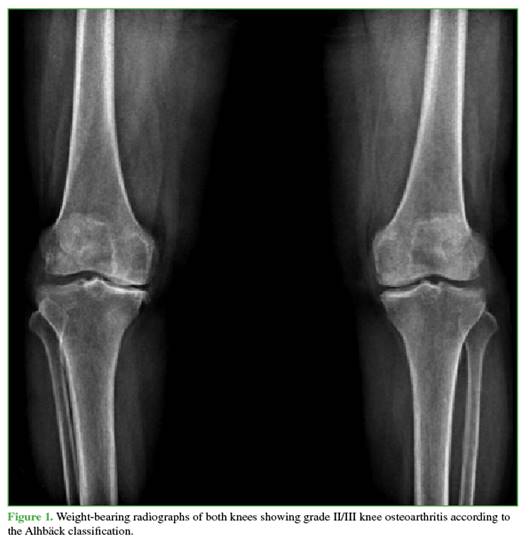

The technique consists of superselective embolization of genicular arterial branches supplying areas of synovial neoangiogenesis, seeking a controlled reduction—though not complete occlusion—of flow to the pathological vessels, in order to decrease inflammation and pain while minimizing the risk of ischemia in adjacent tissues (Figure 4).13